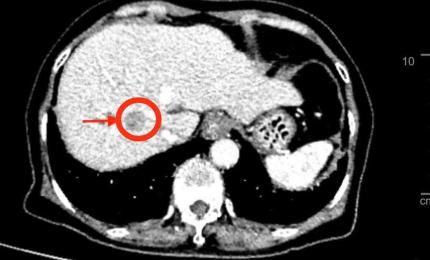

Đau bụng nhẹ, đi khám phát hiện ung thư gan

Cảm thấy đau nhẹ vùng thượng vị, bà Đ.T.A (73 tuổi, ở TP.HCM) đi khám thì phát hiện có khối u gan phức tạp trên nền x